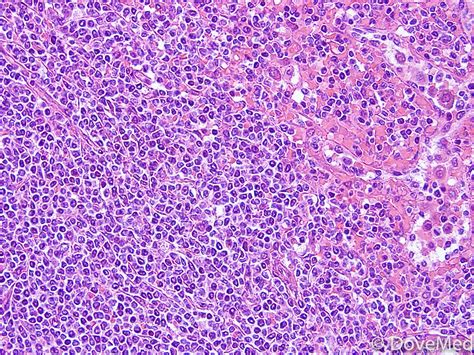

Lymphoma is an umbrella term for a group of blood cancers that affect lymphocytes, a type of white blood cell. Hodgkin lymphoma (hl) is a type of lymphoma in which cancer originates from a specific type of white blood cells called lymphocytes. Lymphoma lymphoma is a type of blood cancer that affects white blood cells called lymphocytes, which are an important part of your immune system. Learn about lymphoma, a cancer that starts in the lymph system. Hodgkin lymphoma can develop anywhere in the body where lymphocytes are found.

Medical Pictures Info - Lymphoma from medicalpicturesinfo.com Hodgkin lymphoma (hl) is a type of lymphoma in which cancer originates from a specific type of white blood cells called lymphocytes. Knowing more will help you understand how lymphoma is diagnosed and possible treatment options. There are many types of lymphoma. Lymphoma is a group of malignant neoplasms of lymphocytes with more than 90 subtypes. Many types of lymphoma exist. The two main kinds of lymphoma are— hodgkin lymphoma, which spreads in an orderly manner from one group of lymph nodes to another. Lymphoma is cancer that starts in the lymph glands or other organs of the lymphatic system. Burkitt lymphoma is considered the most aggressive form of lymphoma and is one of the fastest growing of all cancers.

Lymphoma Signs, Symptoms, Causes, Diagnosis and Treatment from images.ctfassets.net Burkitt lymphoma is considered the most aggressive form of lymphoma and is one of the fastest growing of all cancers. There are two main types of lymphoma, which spread and are treated differently: These cells help fight disease in the body and play an essential role in the body's. These are large, cancerous cells found in hodgkin lymphoma tissues, named for the scientists who first identified them. When you're looking for information about lymphoma, make sure you know which type you want to know about. Symptoms from lymphoma in the chest when lymphoma starts in the thymus or lymph nodes in the chest, it may press on the nearby trachea (windpipe), which can cause coughing, trouble breathing, or a feeling of chest pain or pressure. Lymphoma is a general term for cancers that start in the lymph system (the tissues and organs that produce, store, and carry white blood cells that fight infections). The lymphatic system includes the lymph nodes (lymph glands), spleen, thymus gland and bone marrow.